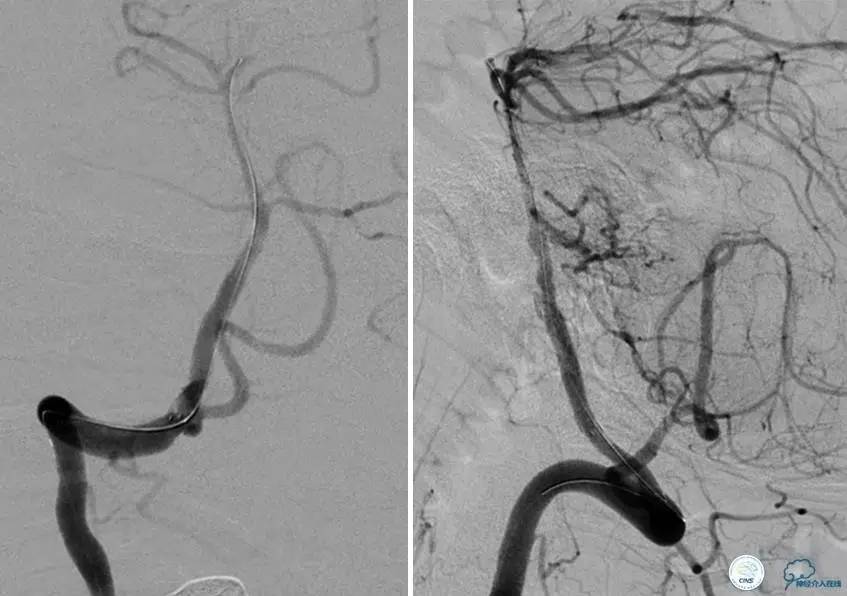

患者:49岁女性,脑梗死30天。

左侧颈内动脉末端闭塞,末端圆钝且有一定成角,开通难度较大,多次尝试导丝才成功穿过闭塞段。

开通效果很满意,术后症状明显恢复。

病例7

患者:反复发作右侧肢体无力、言语不清15天。

导丝很容易通过闭塞段。

顺利置入Wingspan支架,成功开通,手术顺利。